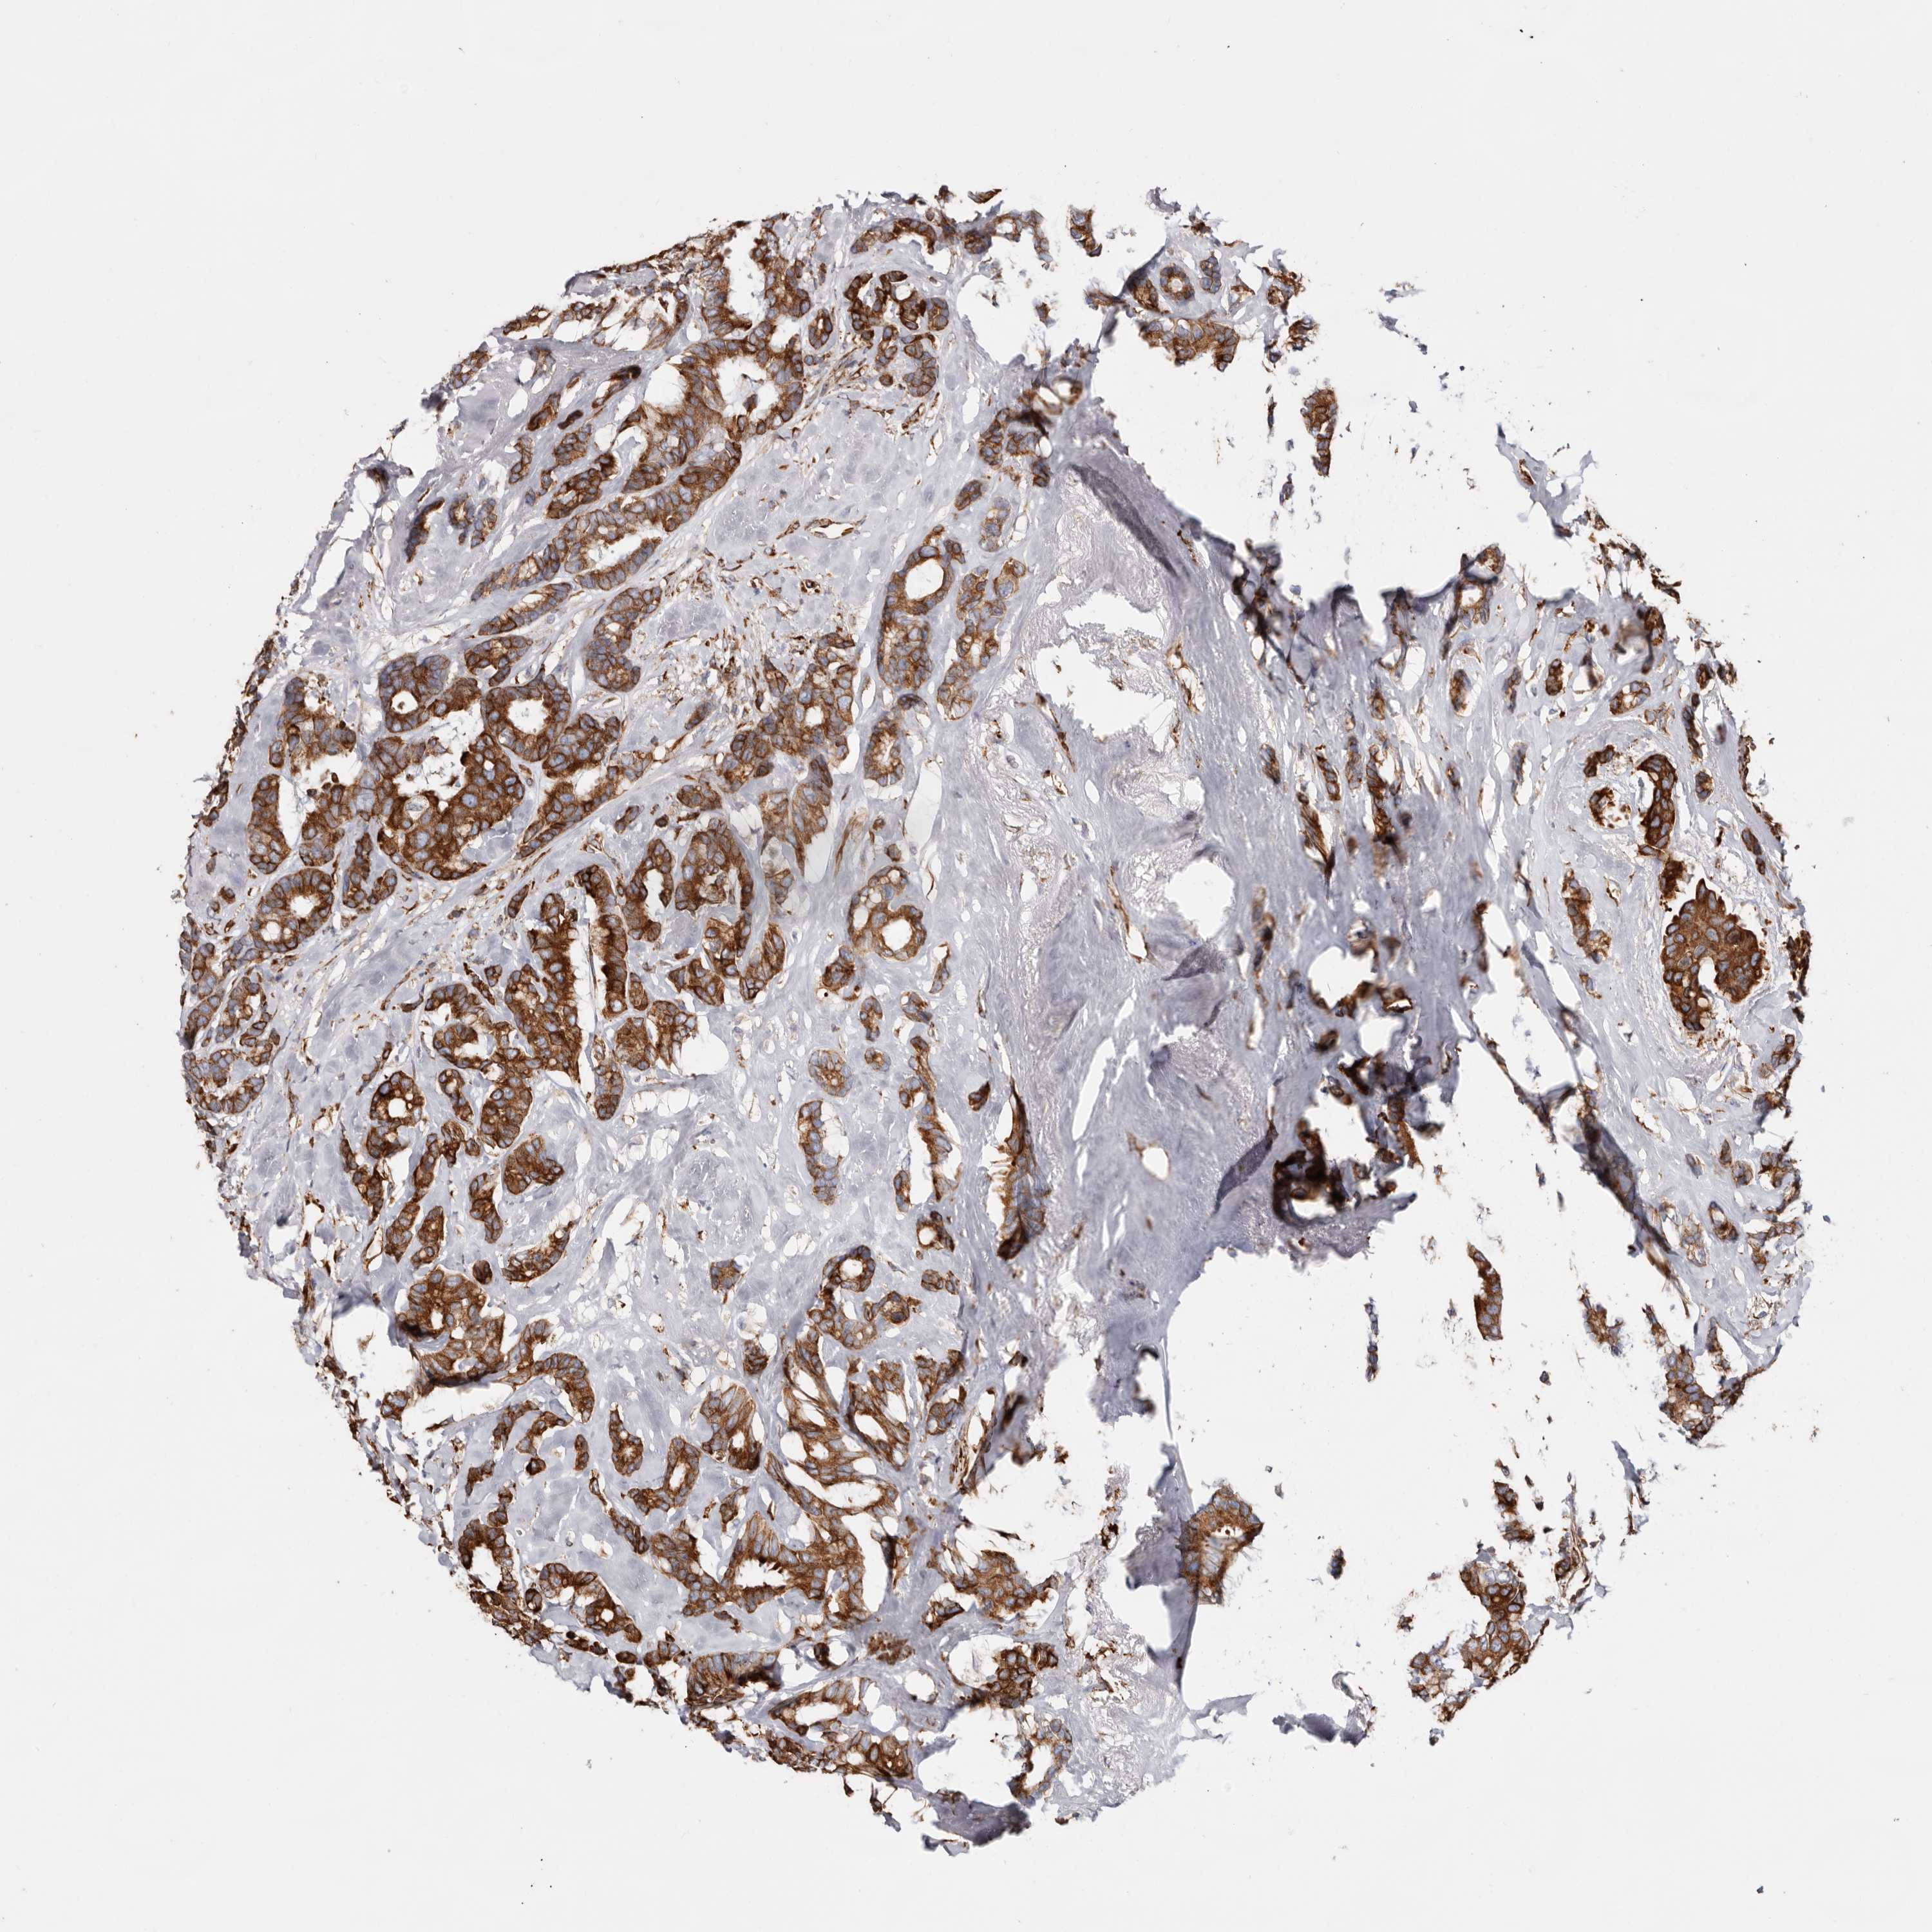

CANCER BREAST CANCER Show tissue menu

BRCA TCGA BRCA VALIDATION PROTEIN EXPRESSION